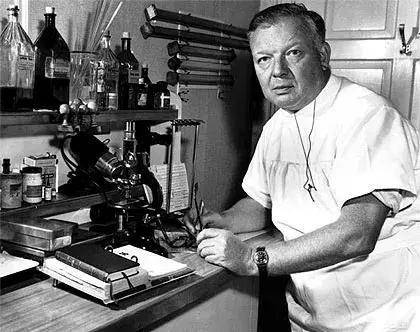

當年,這位年僅25歲的見習醫生沃納·福斯曼(Werner Forssmann),竟偷偷完成了一個震驚世界的實驗。

沃納·福斯曼

1904年8月29日,福斯曼出生於德國柏林。

才24歲,他就通過了國家考試,正式成為一名醫生。

在埃伯斯瓦爾德的一家醫院裡當見習外科醫生,便是他的第一份工作。

福斯曼

年輕的福斯曼